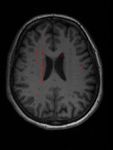

Individuazione lesioni cerebrali da immagini di risonanza magnetica Individuare lesioni da Sclerosi Multipla in immagini di risonanza magnetica: LESIONI MASCHERA Ing. Corinna Vitale 23/06/2021 9

Individuazione lesioni cerebrali da immagini di risonanza magnetica Individuare lesioni da Sclerosi Multipla in immagini di risonanza magnetica: Classificazione & Segmentazione LESIONE = 0 1. Nell’immagine ci sono lesioni? 2. Quali sono i pixel lesionati? INPUT LESIONE = 1 OUTPUT Ing. Corinna Vitale 23/06/2021 10

Costruzione del dataset CARICO LESIONALE BASSO MEDIO ALTO Tre pazienti con diverso carico lesionale Corinna Vitale 23/06/2021 16

Risultati WORST CASE PREDIZIONE GROUND TRUTH Accuratezza lesione 57% - Accuratezza sano 90% Corinna Vitale 23/06/2021

Risultati BEST CASE Escludendo i Falsi Positivi PREDIZIONE GROUND TRUTH Accuratezza lesione 98% - Accuratezza sano 70% Corinna Vitale 23/06/2021